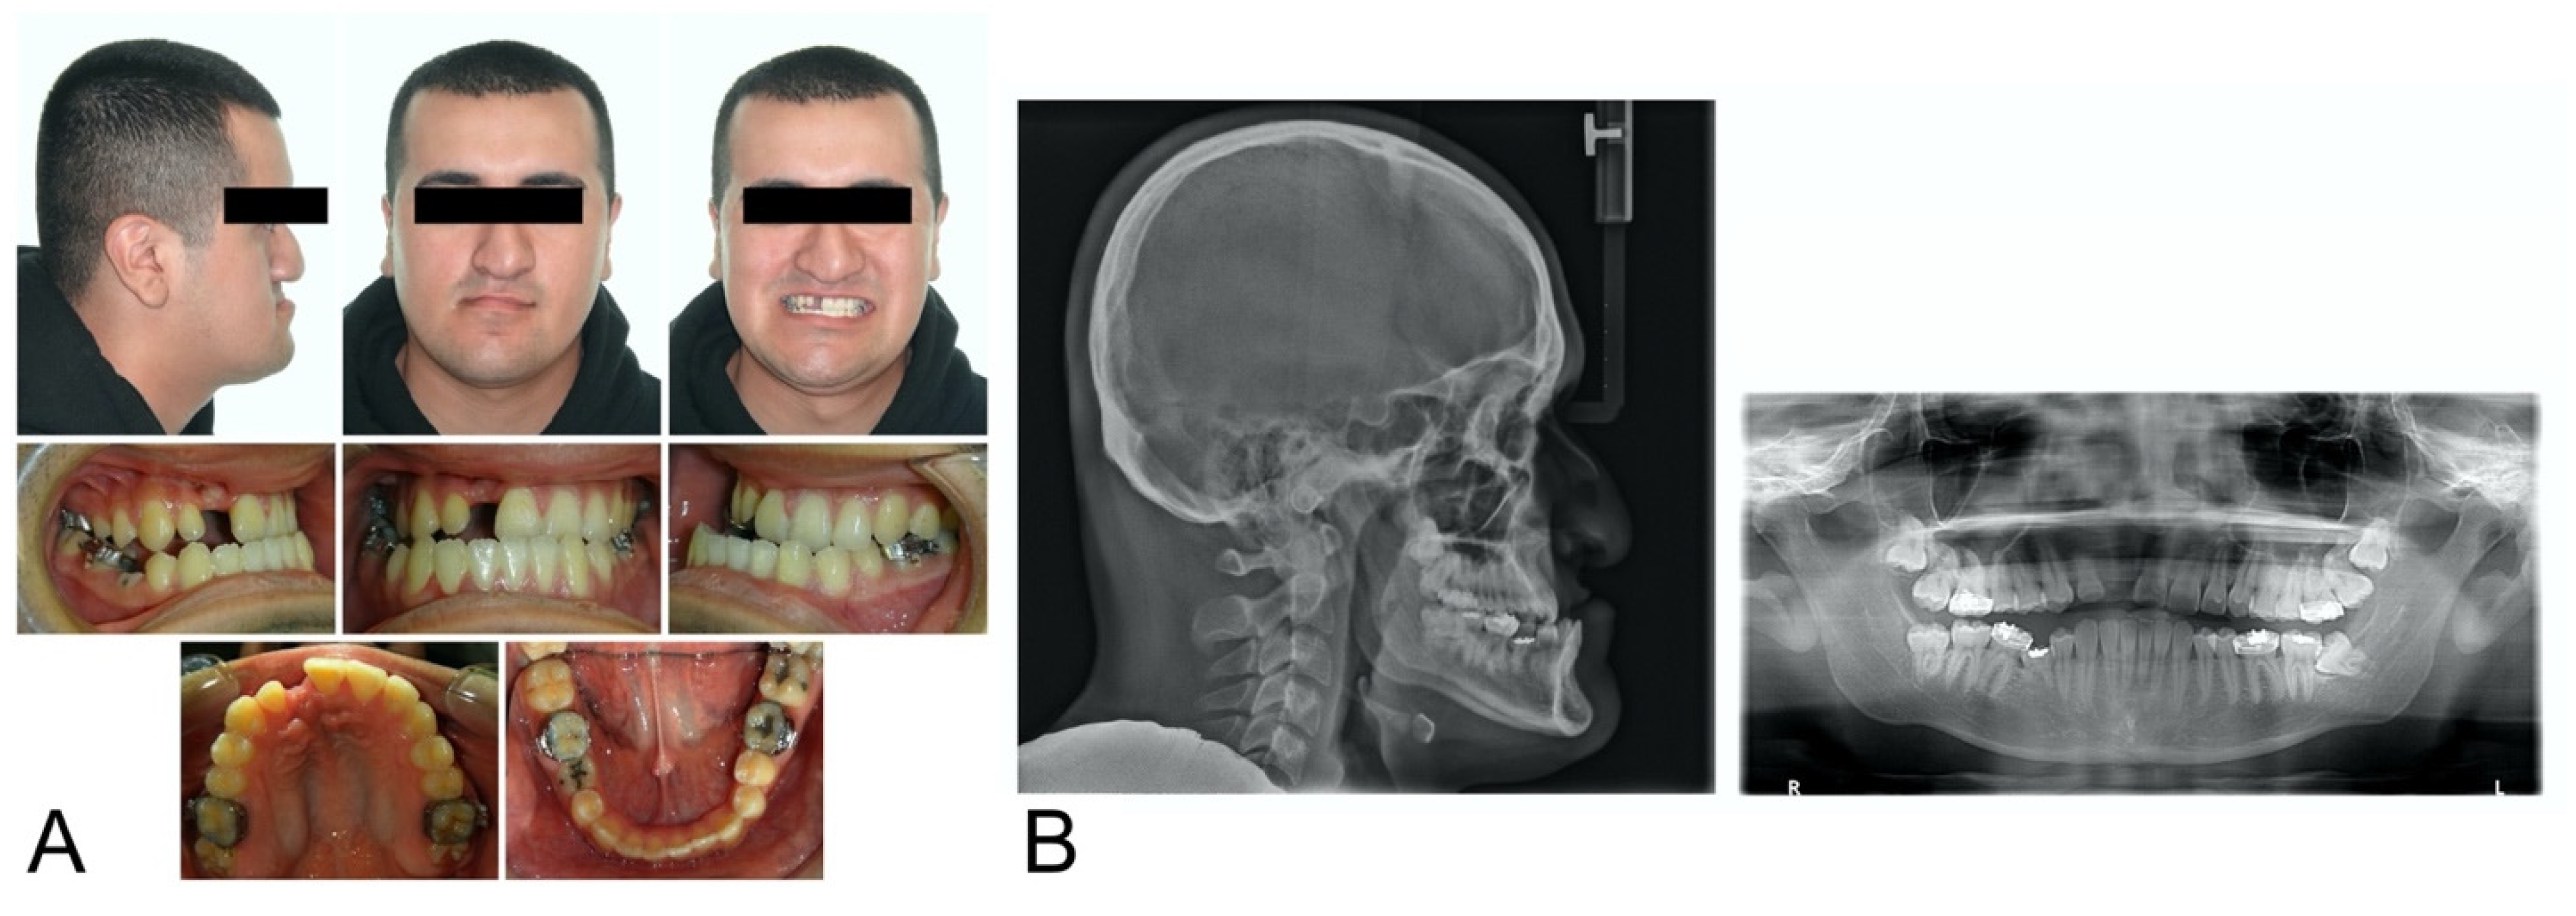

2. Case Description